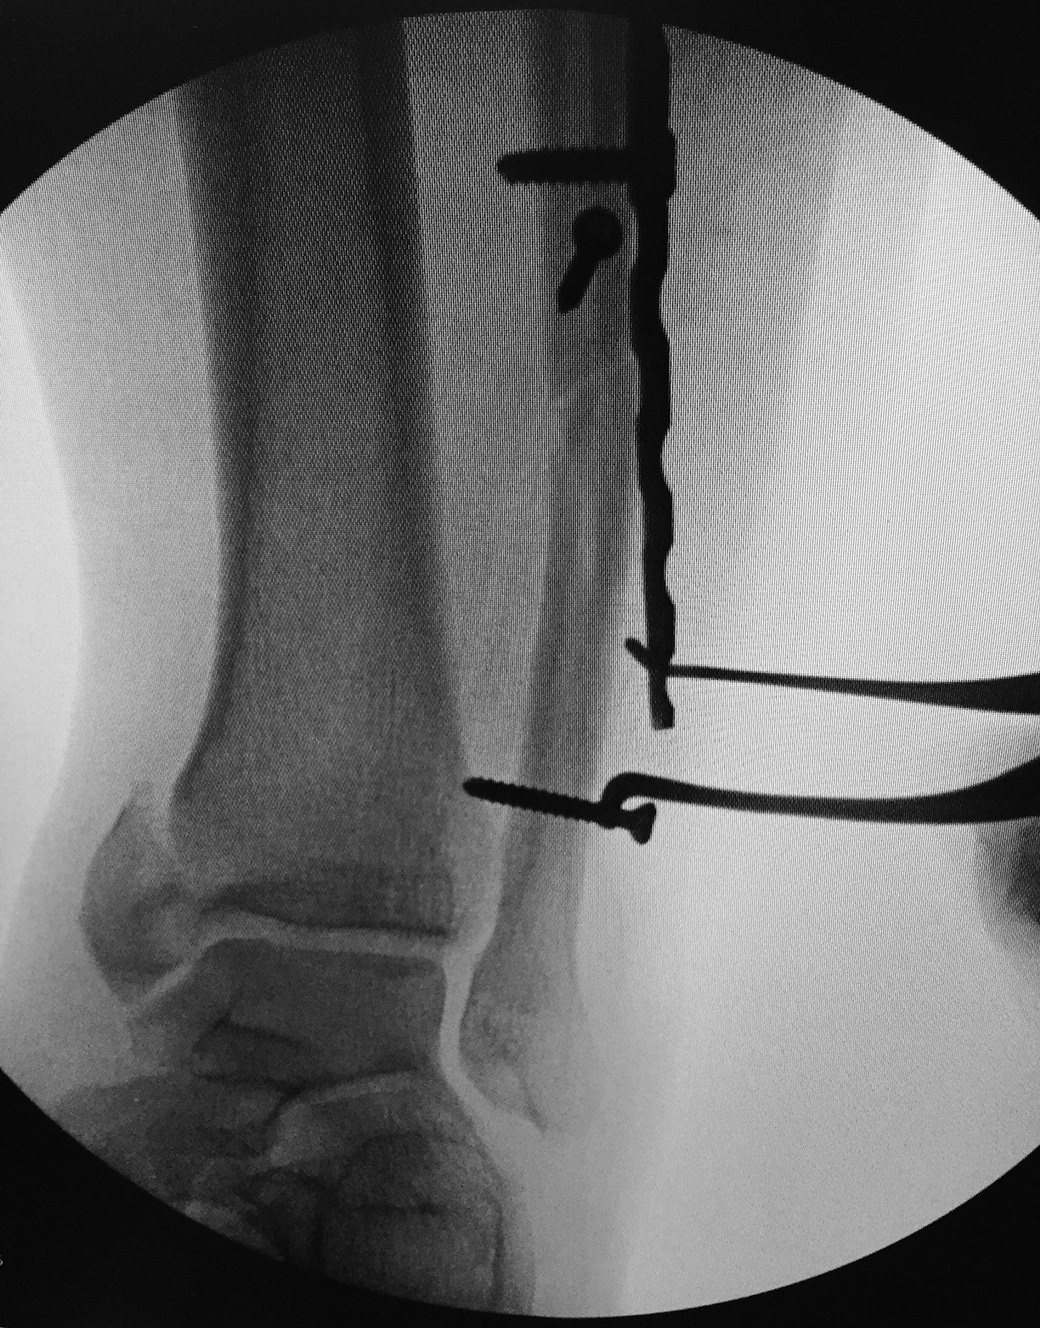

Wixted Fracture Distractor

Designed to provide opposing leverage to help bring the fibula (or other bone) back out to its proper length after it has been shortened by a fracture

A 3.5 mm screw is temporarily placed above a plate, providing a source of leverage for the screw holding end of the distractor. The curved peg-shaped tip is then placed into a hole in the bone plate, and the distractor is activated to bring the bone back to its proper length before fixation.